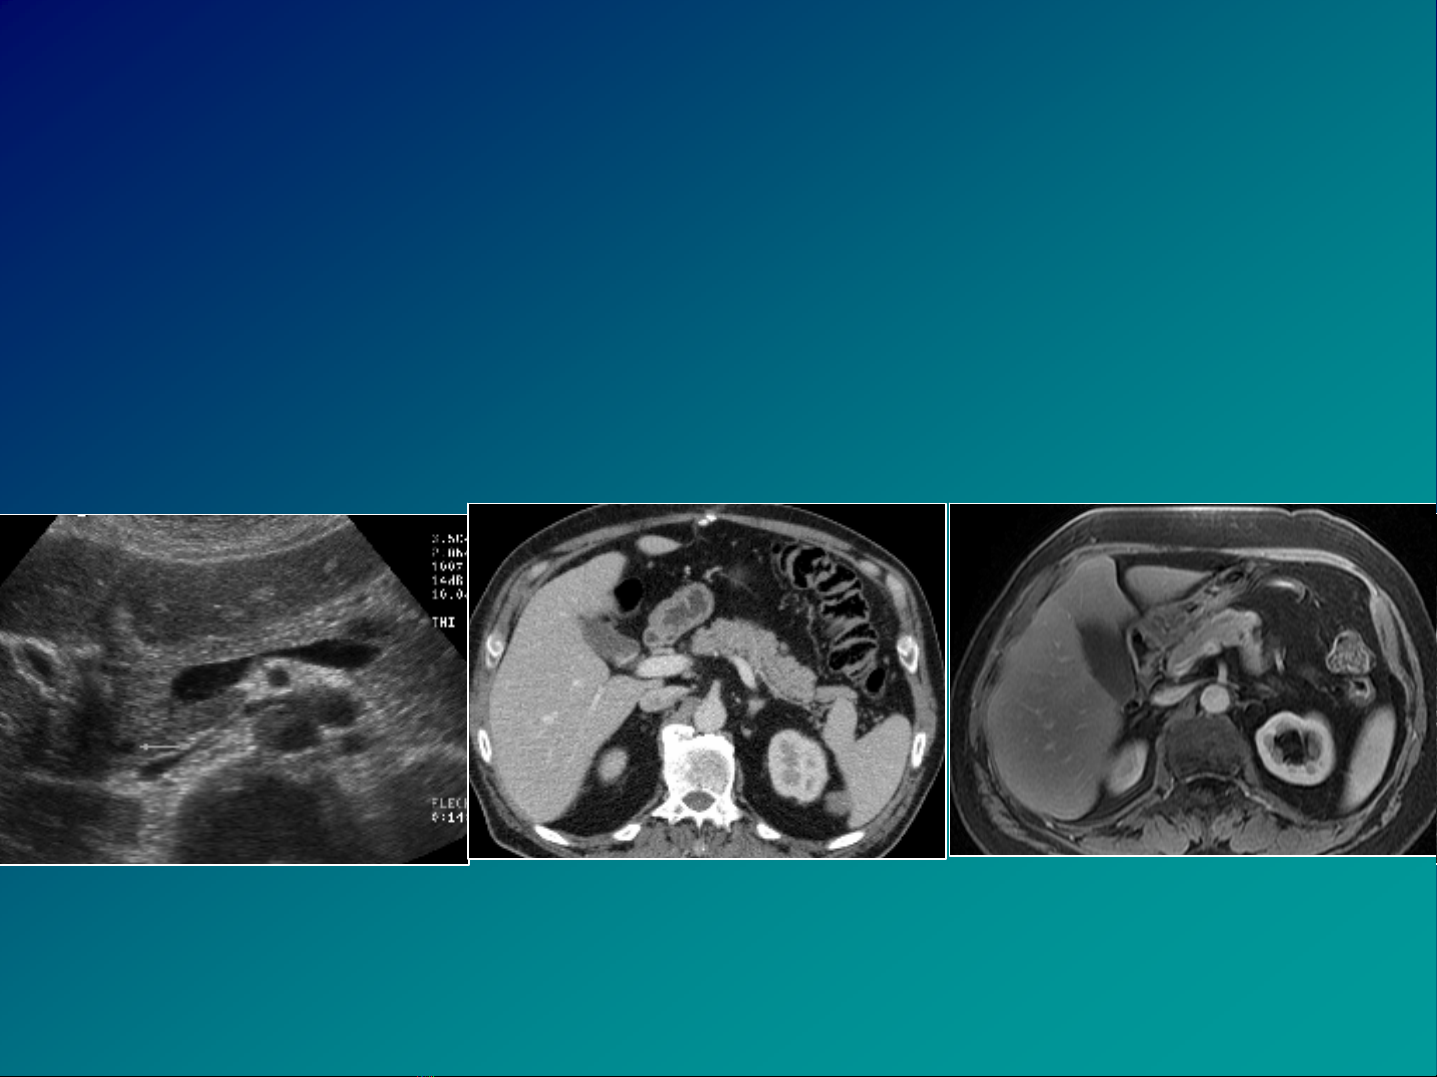

yC¸c tiÕn bé C§HA: CLVT, CHT, SANSoi